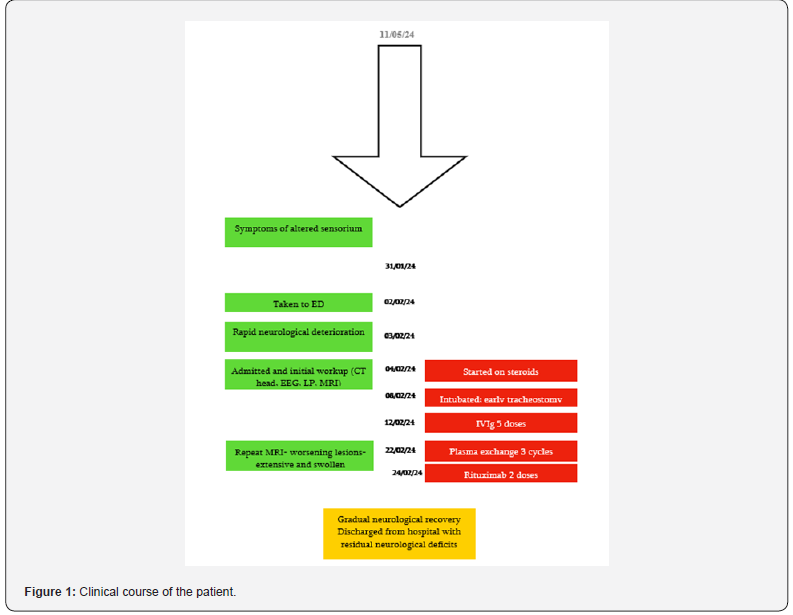

She was intubated for persistently low GCS and to facilitate an MRI. The MRI showed diffuse symmetrical T2/FLAIR hyperintensities involving deep and subcortical white matter, internal capsule, pons, cerebellum with diffusion restriction and enhancement, which was suggestive of acute disseminated encephalomyelitis (Figure 1). She was then started on pulse methylprednisolone. However, after 3 doses, she showed no signs of clinical improvement. Treatment was escalated to a 5-day course of intravenous immunoglobulin (IVIg). As she remained unresponsive, a tracheostomy was performed and transferred to our hospital for the possibility of plasma exchange.

To determine the cause, a whole panel of investigations were sent that included tumor markers, autoimmune panels, paraneoplastic screen, specific antibody screen as well as an extended viral panel and a porphyria screen (Table 1), but all were negative. EEG showed non-specific encephalopathic changes without evidence of seizure activity. Meanwhile, she was started on plasma exchange. No improvement was observed even after 3 cycles. A neuroinflammatory multidisciplinary team meeting concluded that there was clinical and radiological deterioration despite steroids, IVIg and plasma exchange; and a trial of rituximab is warranted. Despite receiving 2 doses of rituximab, her progress was very slow. After around 3 months of total hospital stay, she was discharged on long term steroid and antiepileptic therapy. She still has significant disability and continues to require assistance for activities of daily living (Figure 3).